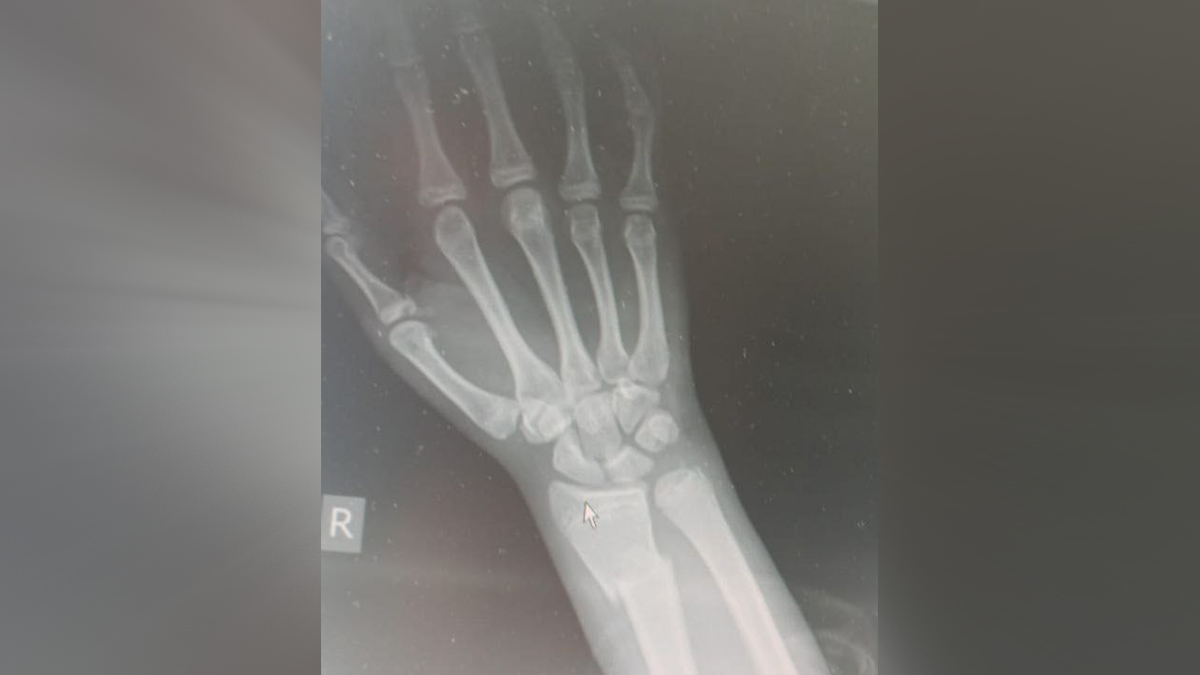

Фото: Пресс-служба Минздрава Московской области

По данным ведомства, 15-летнего юношу госпитализировали в Московский областной центр охраны материнства и детства. У него диагностировали закрытый перелом правой лучевой кости, открытый перелом плюсневой кости правой стопы, ушибленной раной затылка и рваными ранами правой и левой стоп.

Врачи экстренно обработали раны антисептиком, удалили отмершую ткань и наложили швы. Сложный перелом пришлось выпрямлять и фиксировать металлическими конструкциями.